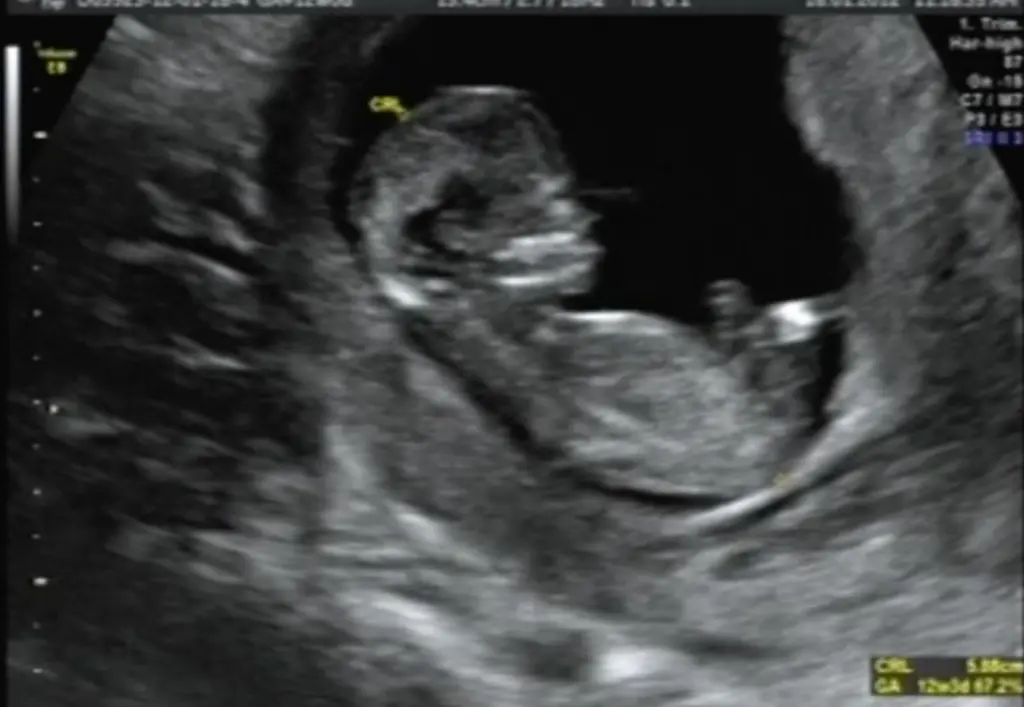

In den frühen Stadien der Schwangerschaft, insbesondere im ersten Trimester, ist das Risiko von Komplikationen durch Niesen erhöht. Dies liegt daran, dass sich die Gebärmutter in dieser Zeit noch stark verändert und das Ungeborene besonders empfindlich ist. Ein starkes Niesen kann zu einer erhöhten Spannung im Bauchraum führen und theoretisch die Gefahr einer Fehlgeburt erhöhen, obwohl dies selten vorkommt.